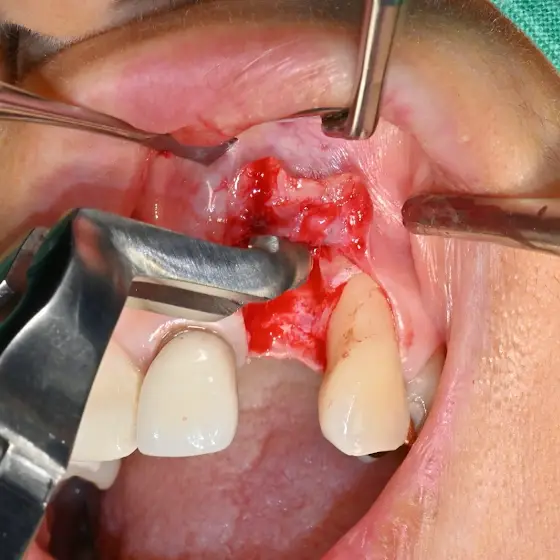

After Intentional Replantation,

A 2-month follow-up radiograph was obtained. The periapical radiolucency was decreased. The patient was satisfied with normal function.